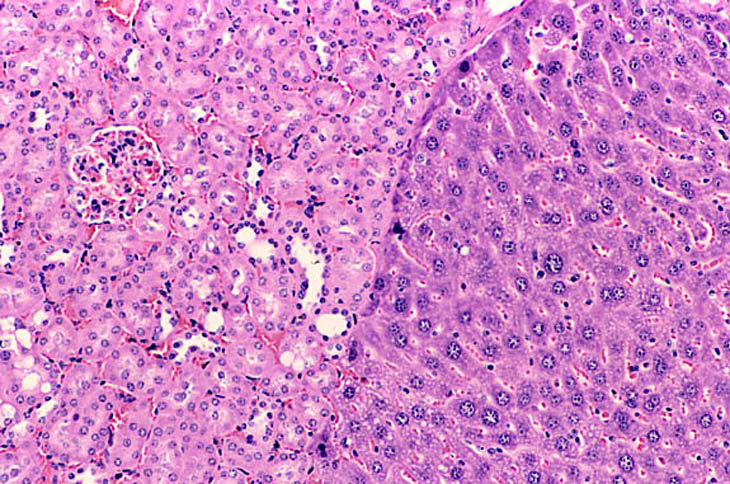

The Digitized Atlas of Mouse Liver Lesions